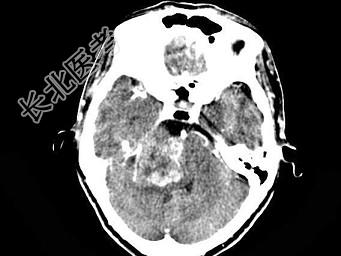

- 单项选择题女,45岁, 右侧听力下降伴行走不稳2个月,根据所提供图像, 最可能的诊断是 ( )

A、右侧脑膜瘤

B、右侧胆脂瘤

C、右侧皮样囊肿

D、右侧神经纤维瘤

E、右侧听神经瘤